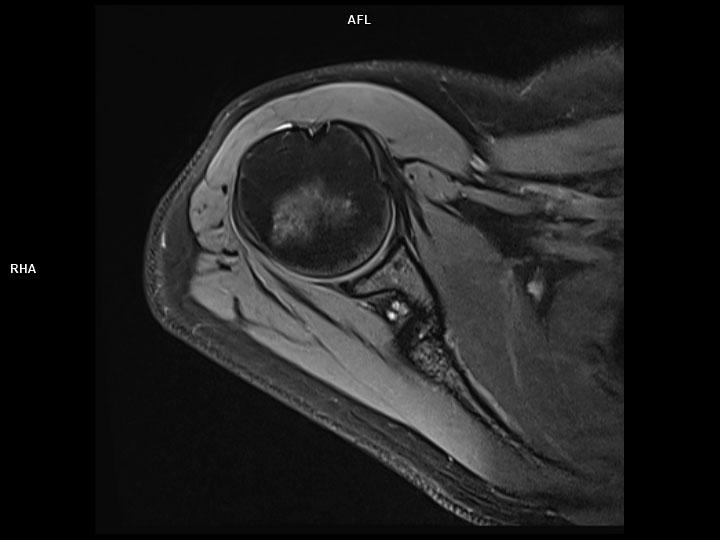

Axial PD FS-MAGNETOM Lumina

Axial PD FS-MAGNETOM Lumina/Coil-UltraFlex 18 Small/Resolution-384/Scan Time-3:00